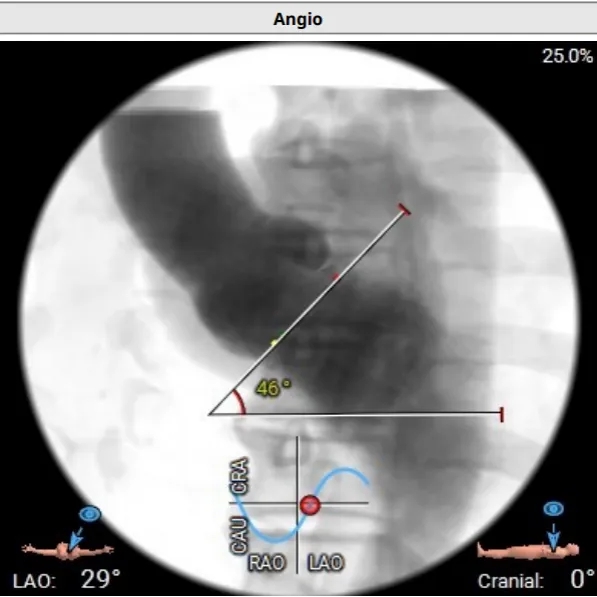

主动脉瓣术前CTA评估

收缩期瓣环直径

27.7mm

收缩期LVOT 2mm

直径 27.8mm

收缩期LVOT 4mm

直径 28.5mm

收缩期LVOT 6mm

直径 29.5mm

SOV:39.6mm

SOV:36.8*35.0*39.2mm

瓣环平面夹角:46°

瓣下MS:2.5mm

左侧冠脉开口高度20.0mm

右侧冠脉开口高度21.2mm